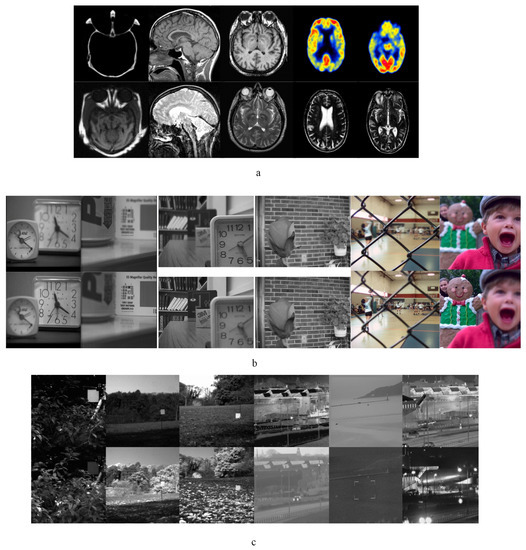

3.2.2. Experiment Results of Multi-Focus Images

3.2.3. Experimental Results of Infrared-Visible Images